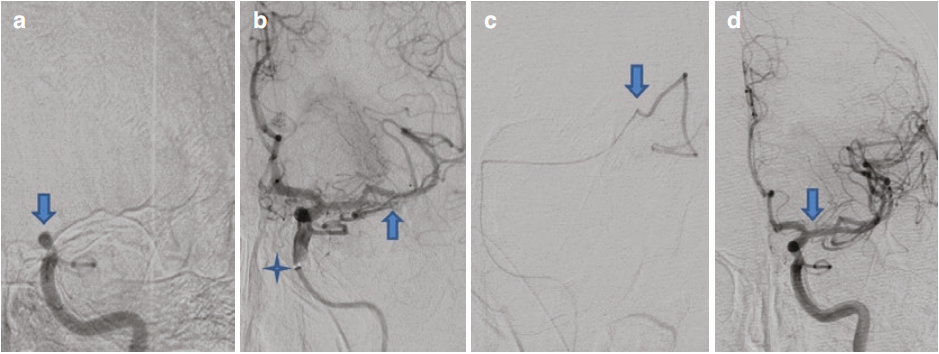

一位52岁的新冠肺炎女性患者,在外院急性起病,出现失语及右侧肢体无力症状后,转至我院。患者需要进行气管插管,进一步的神经影像学检查显示,其左侧大脑中动脉闭塞,且灌注成像存在良好的不匹配特征 。脑血管造影结果表明,患者左侧颈内动脉颈部迂曲,同时伴有同侧左侧大脑中动脉闭塞 。将一根长度为90cm的Neuron MAX 导管,放置于左侧颈内动脉(ICA)颈部迂曲段的近端 。随后,借助Velocity微导管和Synchro 14微导丝,将JET 7抽吸导管向远端推进 。使微导管穿过M1段血栓,超选择性血管造影结果证实,微导管已到达血栓远端的M2分支内 。随后,采用 6mm×40mm的Solitaire取栓支架和JET 7抽吸导管进行机械取栓操作。在释放取栓支架后,将JET 7抽吸导管推进至M1段起始处 。最终的数字减影血管造影(DSA)检查结果显示,左侧大脑中动脉(MCA)供血区实现了完全再通(图 1) 。

图1左侧大脑中动脉取栓术。(a)左侧颈内动脉颈部迂曲,在Neuron MAX导管远端(箭头所示)可见血管痉挛。左侧大脑中动脉M1段闭塞(星号所示)。(b)JET 7抽吸导管越过左侧颈内动脉颈部的迂曲段(箭头所示)。(c)超选择性微导管造影显示,微导管头端(箭头所示)位于血栓远端的 M2 分支内。JET 7抽吸导管进一步向颅内推进(星号所示)。(d)采用取栓支架和抽吸方式完成机械取栓术后,左侧大脑中动脉保持通畅(箭头所示) 。